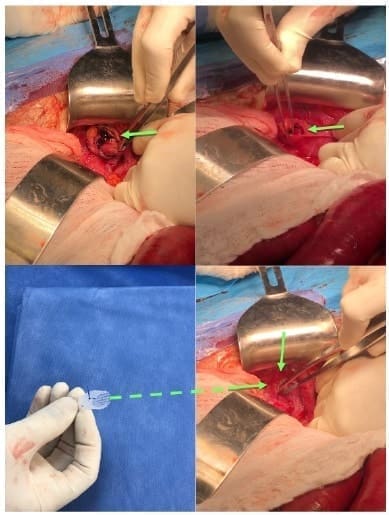

Generalmente, la obstrucción intestinal es la que motiva el tratamiento quirúrgico, por lo que los pacientes son llevados a laparotomía exploratoria, con hallazgos intraoperatorio de hernia obturatriz incarcerada (Figura 7), asociada o no a necrosis del intestino delgado, acorde al tiempo de evolución, lo que obliga a practicar resección intestinal con anastomosis 13,19,31.

Figura 7. Reducción del asa intestinal delgada estrangulada a través de un defecto de hernia obturatriz; obsérvese la estrangulación del yeyuno (flecha verde). Fotografías originales del procedimiento quirúrgico tomadas por los autores.

La técnica del tapón con malla (Figura 8) necesita una adecuada calibración y ha logrado menos complicaciones de compresión del paquete neurovascular, tales como neuralgias difíciles de tratar 12, rechazo a cuerpo extraño y recurrencia herniaria.

Figura 8. Disección del saco herniario y corrección del defecto con técnica de tapón de malla de polipropileno (flecha verde). Fotografías originales del procedimiento quirúrgico tomadas por los autores.